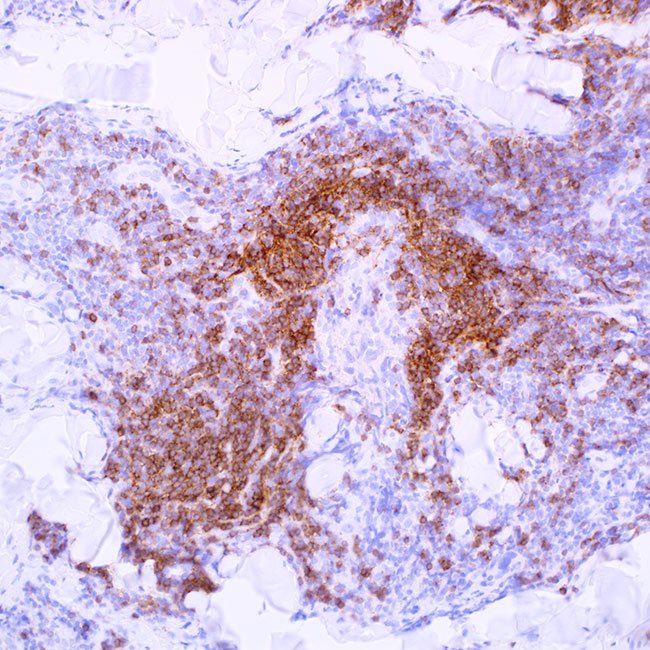

IgD (EP173)

Controltonsil